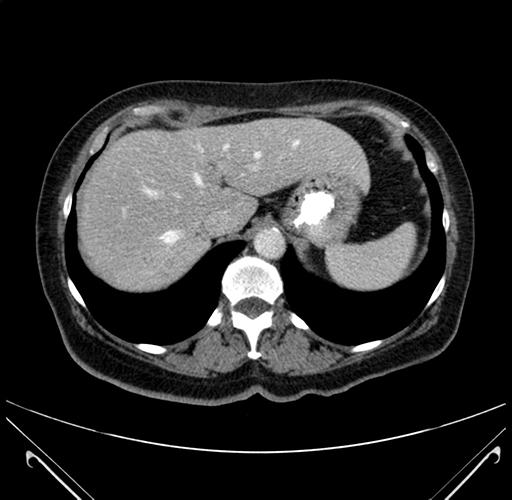

Axial Venous